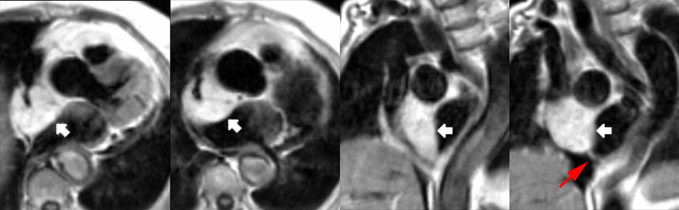

– Il importe de bien connaitre la séméiologie propre aux séquences dont on dispose pour apprécier les jets de perte de signal liés aux flux rapides en séquence ciné.

– Les séquences de cartographie de flux ‘through-plane’ et ‘in-plane’ permettent une bonne approche hémodynamique des valvulopathies.

– Insuffisance aortique : recherche de bicuspidie et quantification de la fraction de régurgitation par l’IRM sont fiables.

– Rétrécissement aortique : Recherche de bicuspidie fiable, possibilité de quantification de la surface valvulaire et du gradient systolique.